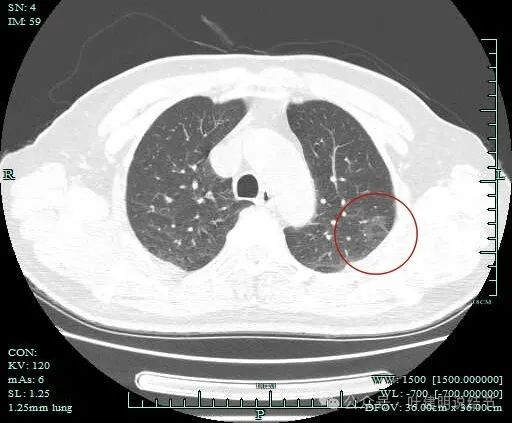

病灶出现,范围较大,密度较低,但轮廓较清楚。

病灶肺表面近,整体轮廓与边界清,表面不平,灶内有小空泡征。